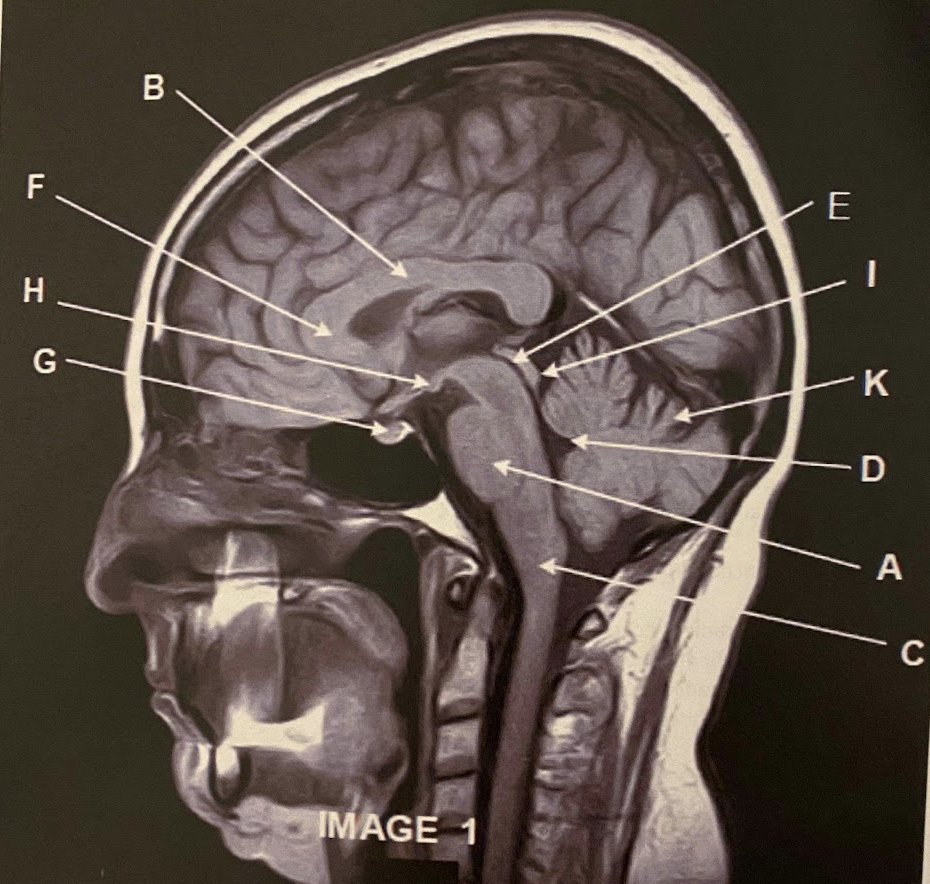

The sagittal scan, demonstrates typical hyper intense tendril-like projections in the corpus callous characteristically seen in patients with what disease?

C) Multiple Sclerosis

What anatomy is letter A pointing to?

Pons

What anatomy is letter B pointing to?

Corpus Callosum

What anatomy is letter C pointing to?

Medulla Oblongata

What anatomy is letter D pointing to?

Fourth ventricle

What anatomy is letter E pointing to?

Aqueduct of Sylvius

Q

Genu of the corpus callous

Pituitary

Mammillary Bodies

Quadrigeminal plate

This image is non-contrasted. It was acquired using a _______ sequence

C) FLAIR